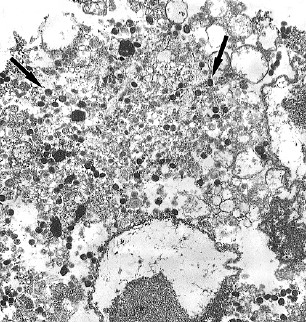

The aim of the study is to confirm the first case of monkeypox in Russia, to isolate and sequence a new strain of monkeypox virus (MPXV), and to assess its sensitivity to the 7-[N-(4-trifluoromethylbenzoyl)-hydrazinocarbonyl]-tricyclo-[3.2.2.0^2,4]non-8-en-6-carboxylic acid (NIOCH-14) antipox drug.

Materials and methods. The biological materials obtained from the affected area of the skin (contents of vesicles), a nasopharyngeal smear, sputum and venous blood from a patient with suspected monkeypox were used. The disease was confirmed by PCR followed by determination of the nucleotide sequence of viral DNA by sequencing. Isolation of the new MPXV strain from clinical samples was carried out in Vero E6 cells. The antiviral effectiveness of NIOCH-14 against the new MPXV strain was assessed using an adapted spectrophotometric method.

Results. A diagnostic study of the biological samples of a patient who returned from a tourist trip to European countries with complaints of skin rashes all over the body revealed MPXV DNA. A new strain of MPXV was isolated from vesicles in Vero E6 cells, and the genomic sequence MPXV-pustule S45 was assembled using high-throughput parallel sequencing (NGS).

Discussion. The effectiveness of the finished dosage form of NIOCH-14 against the new strain of MPXV based on the results of determining the 50% virus inhibitory concentration (IC50) was 0.02 μg/mL, and the selectivity index (SI) was > 15,000.

Conclusion. In this study, the pathogen of monkeypox was detected and identified using real-time PCR, NGS and electron microscopy, and the first imported case of this disease in Russia was confirmed. It has been proven that the drug NIOCH-14 exhibits high antiviral activity in vitro against the new MPXV strain.